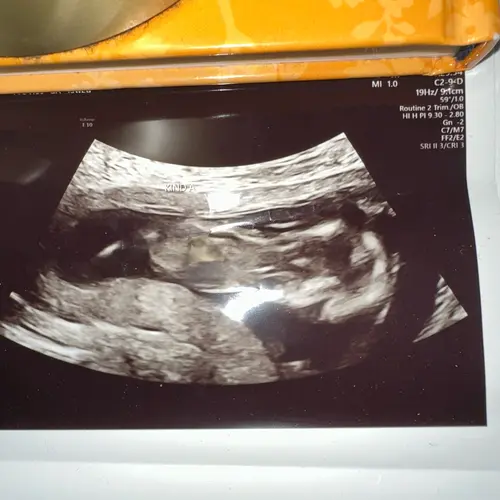

Ik heb alleen deze nog maar denk dat deze ook niet duidelijk genoeg is

Hmmm twijfel hoor.. denk een jongen

Ik heb hier een betere foto..

Denk jongetje